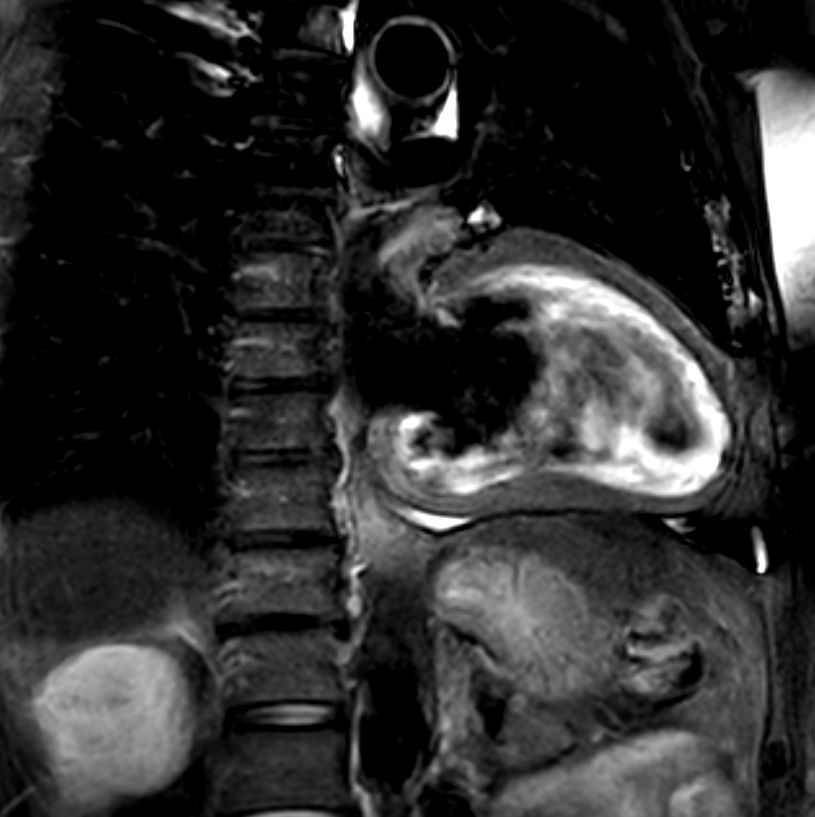

Myocardial infarction with T1/T2 Mapping

Patient with myocardial infarction. ExamCard includes functional imaging, dynamic cardiac MR studies, black blood imaging and non-invasive assessment of myocardial tissue characteristics. Post-processing is performed on IntelliSpace Portal (ISP12), designed to reduce your time to report through optimized workflows and results automation.

2 chamber view T2w Black Blood

Short axis view T2w Black Blood

4 chamber view T2w Black Blood